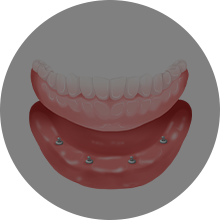

김○미님 틀니 전

2019년 3월

김○미님 틀니 후

2019년 4월